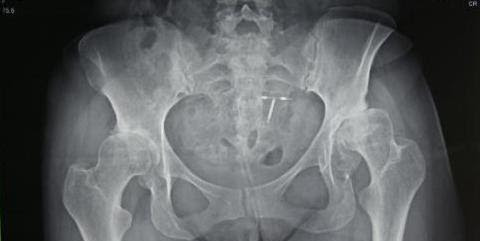

Marciela's x-ray prior to her 2018 surgery.

Marciela Arevalo was one of our patients during the 2018 CAMTA mission, where she received a bilateral hip replacement. Her one year follow up with Dr. Tim Kostamo went so well she came out of his office dancing in her high heels! She expressed her thanks to the team and plans to keep dancing! We love these success stories!